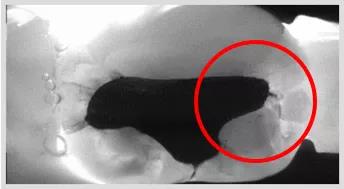

龋齿探测

龋齿探测仪检查:在龋齿探测仪的咬合面的图像上显示,近中合面存在低密度的阴影区。判断有邻面龋。